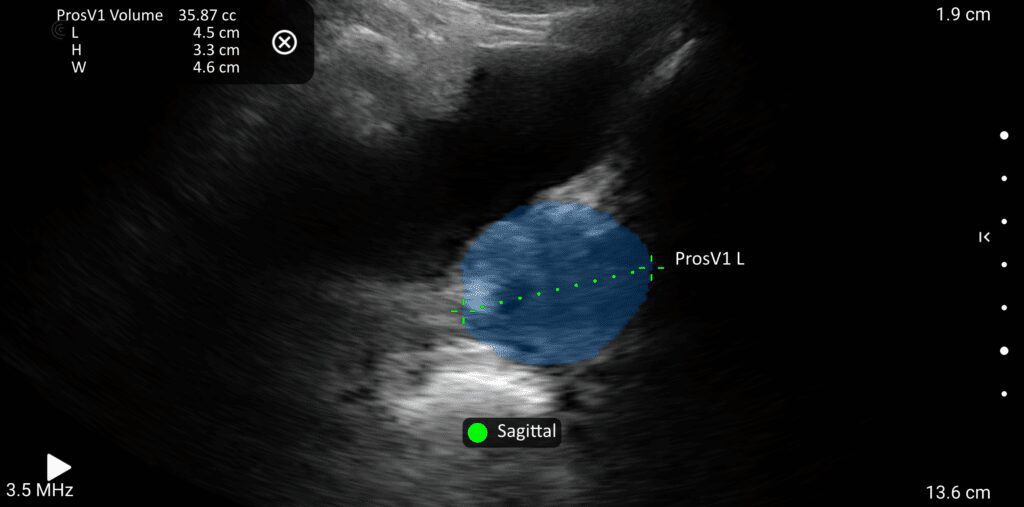

The image quality is amazing, it’s easy to use, and perfect for assessing muscles involved in maintaining continence.